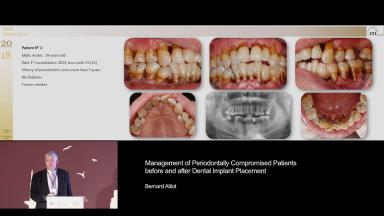

The lecture concludes with several clinical cases where the speaker covers the treatment planning process for periodontally compromised patients who require implant therapy, and their long-term management following placement.

- recognize that patients with a history of periodontal disease demonstrate a higher risk of peri-implant diseases

- identify risk factors for implant therapy which may affect treatment outcomes

- recognize that supportive periodontal therapy is the key factor in enhancing long-term survival of implants in periodontally compromised patients